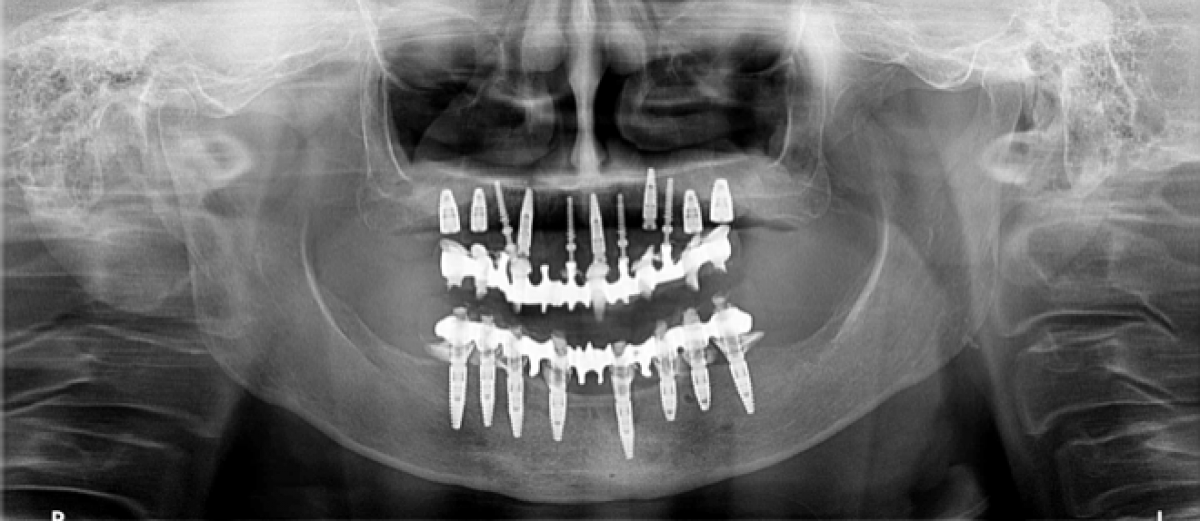

Thanks to the implant-prosthetic design carried out in the pre-surgical phase, it is possible to place the temporaries in the same session as the surgery, immediately regaining a correct occlusion, vertical dimension and satisfactory aesthetics. Once 4 months have passed after implant surgery and the implant sites and soft tissues have healed completely, we are ready to proceed with the definitive prosthetic phase.

First of all, the implants in the upper arch that could not be possible immediately load, are uncovered, and then new impressions are taken with an intraoral scanner that will give the laboratory the exact position of all the implants and the new state of the soft tissues.

Once we have the new temporary prostehesis, it is possible to remove the mini implants, and proceed with the production of new prototypes with which we will make the final evaluations and modifications. (PICTURE 5)

Before finalizing the restoration, a cobalt-chrome bar is designed by CAD and then tested in the mouth on the turrets to check the passivation, also radiographically. (PICTURE 6)